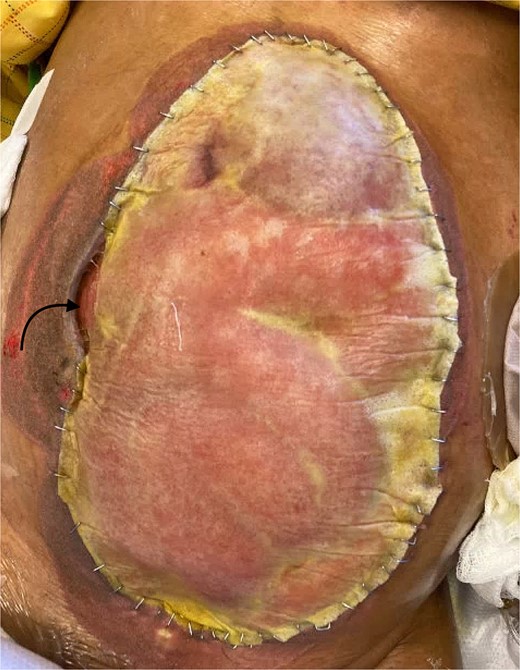

On hospital Day 31, BTM™ was placed on top of partially granulated intestine and liver. A hole on the BTM™ was trimmed to fit around the small bowel fistula and a Malecot™ drain placed to assist with fistula control (Fig. 2). A wound vacuum was applied on top of the BTM™ to keep it adherent to the granulated abdominal contents as well as fluid accumulation from non-granulated areas. When the BTM™ became sufficiently adherent to the abdominal content, the vacuum device was removed and an ostomy bag was placed directly to the BTM to control the output. With time the EAF resolved. Split thickness autograft was performed on hospital Day 68 (Fig. 3), and the patient was discharged after a total of 123 days. Figure 4 shows the healed image on the day of discharge.

Novosorb BTM on the abdomen with the laminte layer still on. The black arrow represents the location of the fistula.